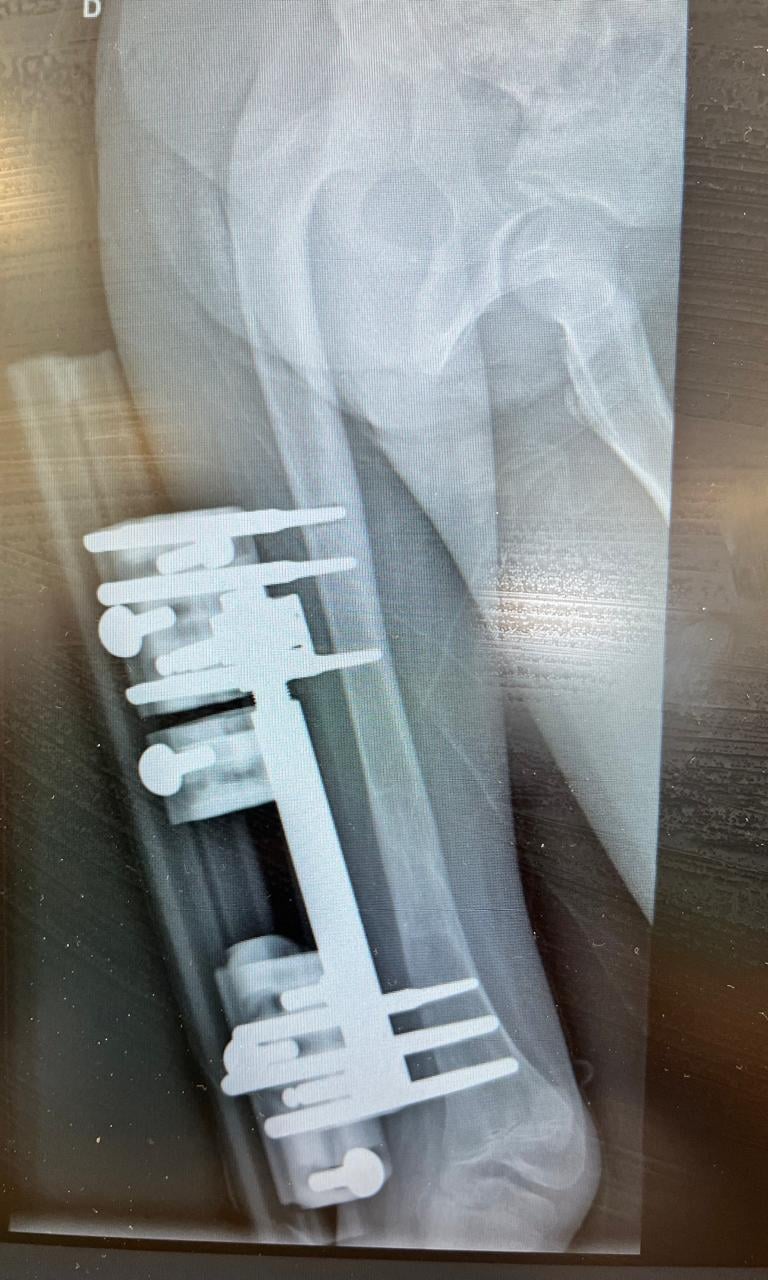

Sequelas pós-trauma ou fratura

Pseudoartrose ou falha de consolidação óssea